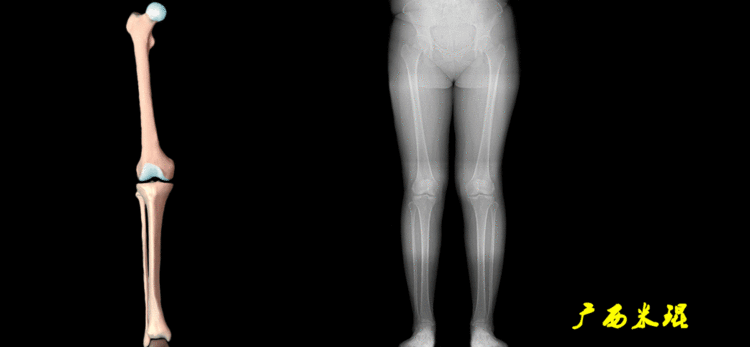

2、画出下肢的轴线确定髋关节、膝关节、踝关节的中心点后,我们才能了解下肢的几个轴线。(1)解剖轴股骨和胫骨的骨干中线为解剖轴,股骨解剖轴和胫骨解剖轴的夹角正常值为174°±1°。

(2)机械轴机械轴是连接近端和远端关节中心点的直线。

机械轴要分前后位及侧位,站立前后位(也就是冠状面)股骨头中心与踝关节中心的连线通过膝关节中心,这是下肢的机械轴线,也就是下肢力线,常说Mikulicz线。冠状面的力线评估在临床工作中最常用、最基础、最重要。

站立侧位(矢状面)股骨头中心与踝关节中心的连线也通过膝关节中心,这也是下肢的机械轴线,这也是下肢力线。

(3)垂直轴也就是下肢的负重轴,它是身体的纵轴线,与地面垂直,由于双髋比双踝的距离宽,所以垂直轴与下肢力线(机械轴)存在3°的外翻。

开始接触时可能我们对这些轴有点混乱,通过下面的这张图片就能清楚的了解下肢几个轴之间的关系。